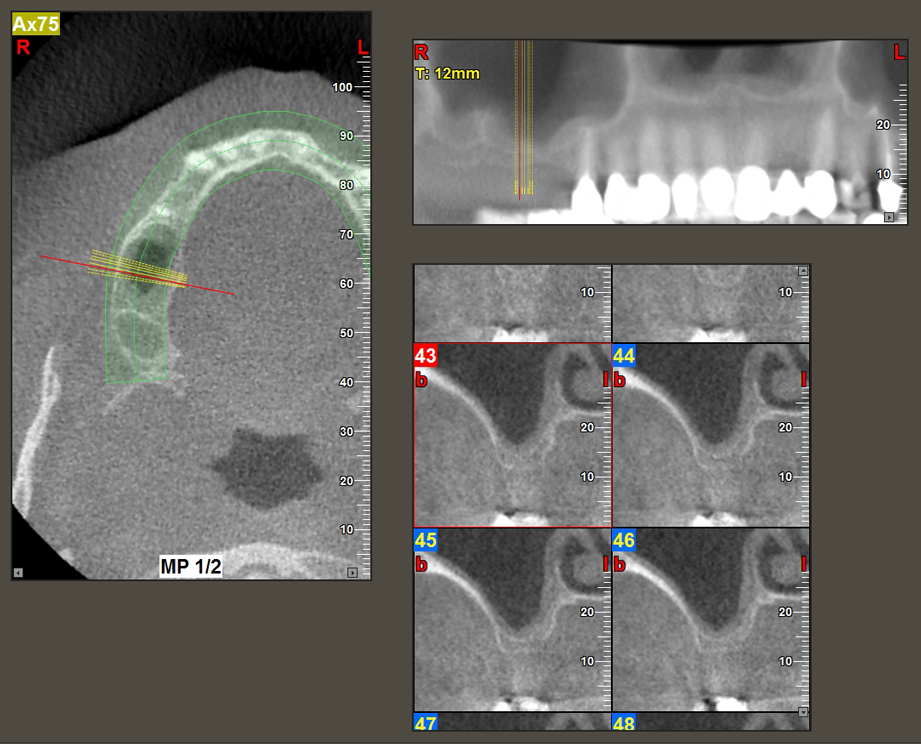

The I2A instrument (diameter 2.0 mm) was then used to perforate the sinus floor intermittently and on the smallest scale possible. This special piezosurgical method ensures that the Schneiderian membrane is not damaged. When the Z25P was used, the membrane was already lifted slightly by the coolant supplied via the instrument tip (Fig. 3). The coolant quantity was just 50% in order to avoid high pressure in the implant bed.

Implant bed preparation and augmentation

Following an intermediate check (Fig. 4) a further preparation step was performed (Fig. 5). Afterwards, the hydraulic Z35P instrument was used to lift the membrane to the desired position (Fig. 6 and 7). This was followed by further piezosurgical preparation of the implant bed, concluded with a rotary bur and shoulder milling cutter up to the implant diameter of 4.8 mm. Before the implant was inserted, the augmentation material (particle size approx. 0.8-1.6 mm) was introduced underneath the Schneiderian membrane (Fig. 8).